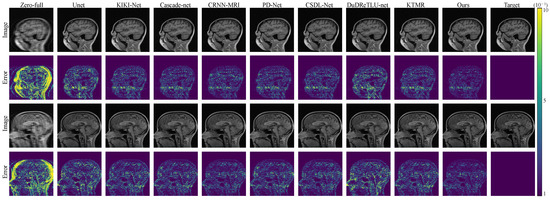

To visually illustrate the effectiveness of our approach, we present comparison results for 4× and 8× acceleration rates in Figure 2 and Figure 3. These figures clearly demonstrate that our framework excels in preserving intricate structures, creating more natural and intricate texture features, and producing clearer and more realistic reconstructed images compared to other methods. Furthermore, our method excels in achieving high-fidelity reconstructions even when dealing with highly under-sampled measurements. Figure 2 and Figure 3 also display error maps corresponding to various comparative methods, highlighting that our approach yields fewer errors at different under-sampling rates.

As shown in Figure 4 and Figure 5, both in the error maps and the reconstructed images, our algorithm demonstrates smaller errors and more accurate texture structures, which is similar to the results observed in the FastMRI dataset.

Figure 4. The reconstruction results and error maps are compared among 8 algorithms under 4× acceleration on the Calgary-Campinas dataset.

Figure 5. The reconstruction results and error maps are compared among 8 algorithms under 8× acceleration on the Calgary-Campinas dataset.